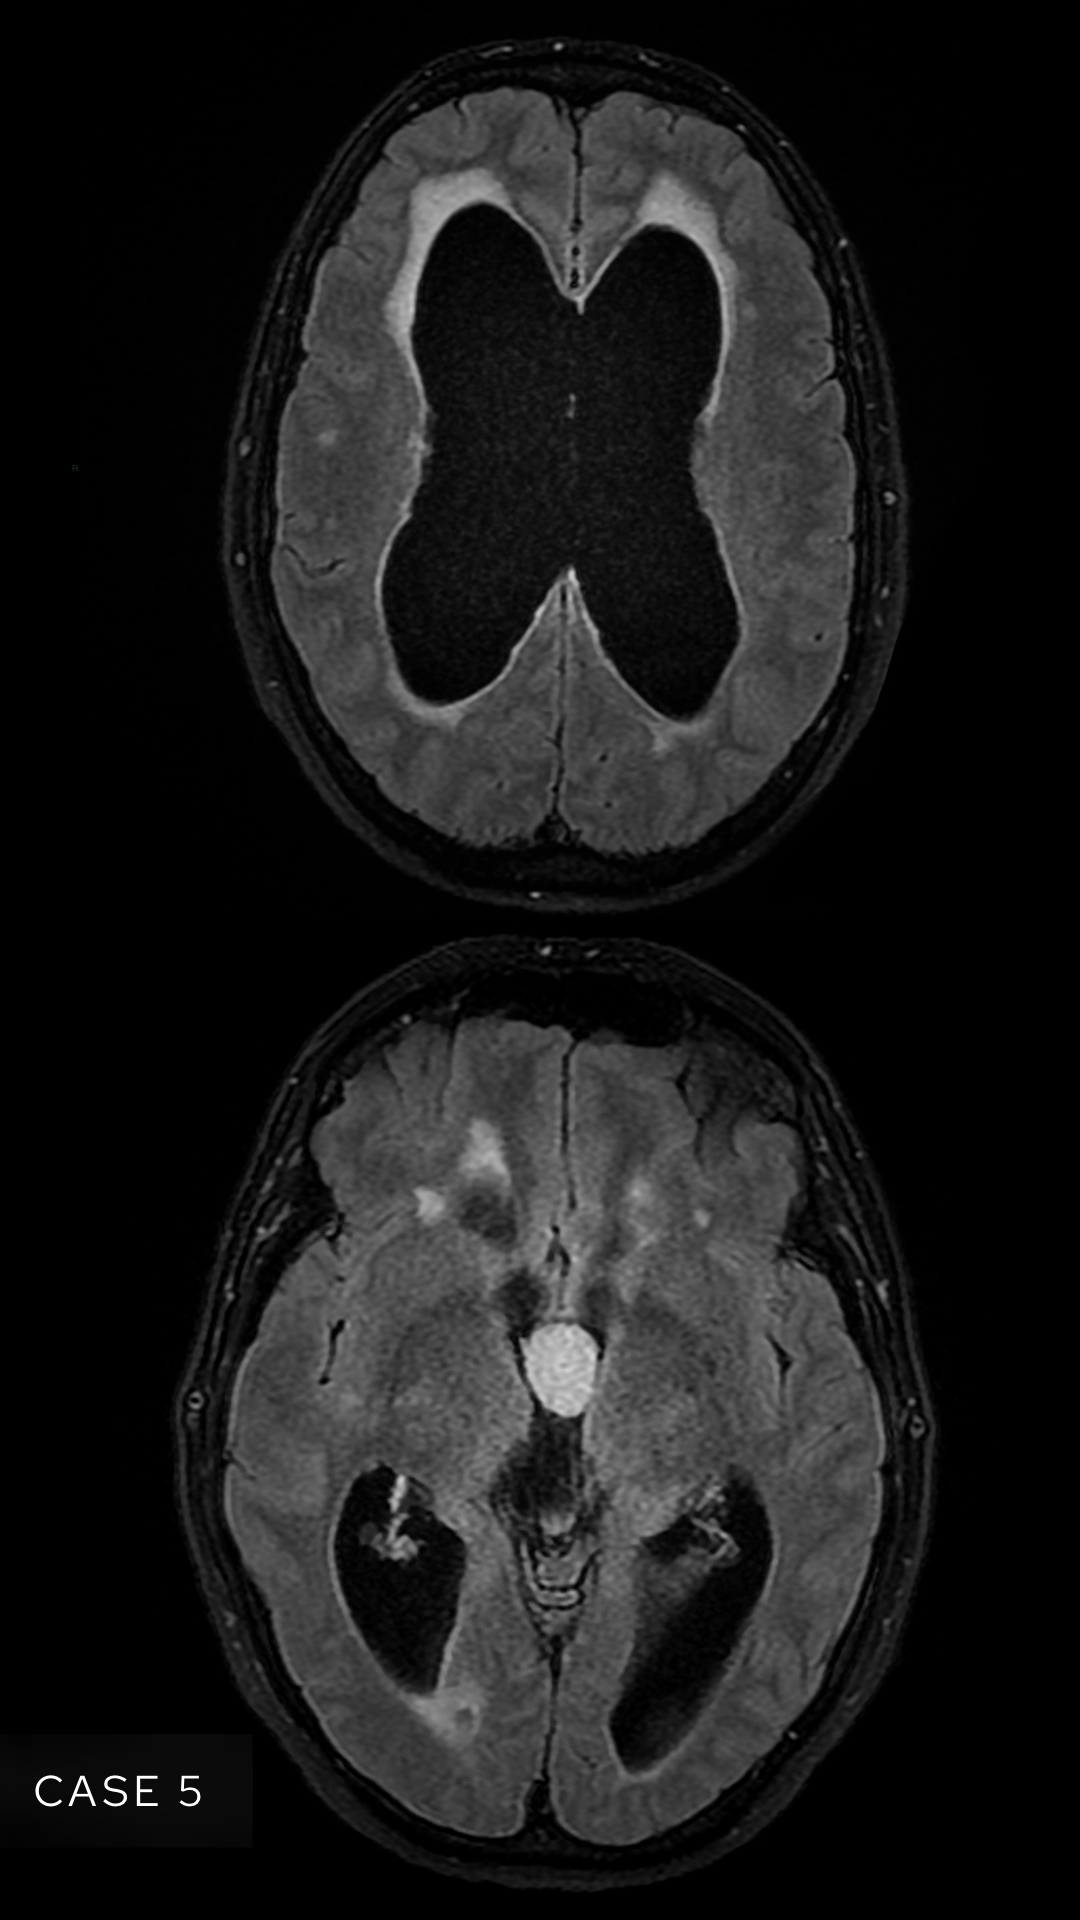

Case 5

A female in her 50s presents with gait disturbance. Here are two images from a MRI head (FLAIR sequence). What is the most likely diagnosis?

Choose from one of the following options: